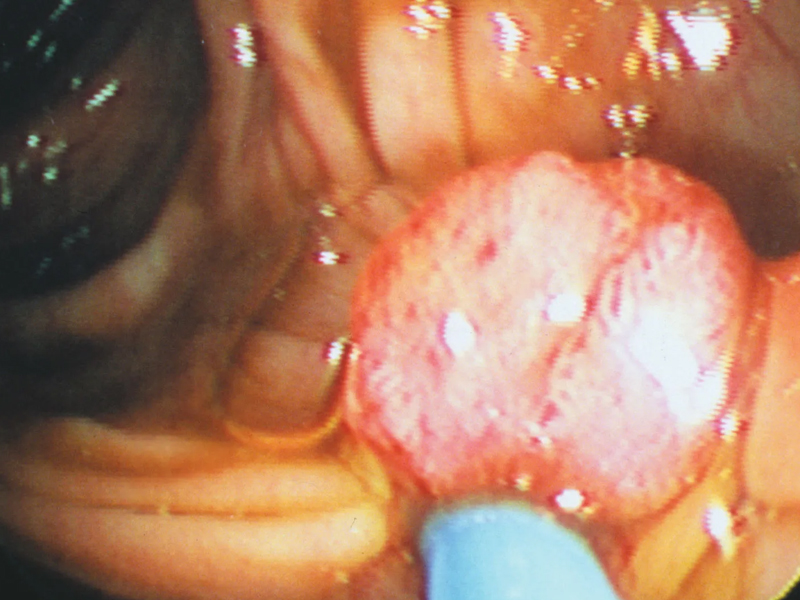

前列腺癌是在前列腺中有異常細胞生長的癌症。前列腺是男性獨有的一個腺體,其體積類似一個胡桃的大小。它的位置在膀胱與尿道交接的地方。 ![]() 前列腺癌的病因不明,並且目前沒有明確的預防策略來降低患前列腺癌的風險。前列腺癌是繼非黑色素瘤皮膚癌之外最常見的癌症,每年有超過 16,000 名男性被診斷為前列腺癌。它通常影響老年男性,很少見於 45 歲以下的男性。 診斷患上前列腺癌的機率是多少? 40 多歲的男性為 554 人中有 1 人 50 多歲的男性為 45 人中有 1 人 60 多歲的男性為 15 人中有 1 人 70 多歲的男性為 11 人中有 1 人 有近親患有前列腺癌的男性其診斷的機率加倍。與那些有較年長親屬患有前列腺癌的男性相比,有近親 在 60 歲之前患上前列腺癌的男性的患病風險較高。由於有家族史而有高風險的男性應該與他們的醫生商量。 前列腺癌有甚麽症狀? 早期前列腺癌可能沒有任何症狀,儘管前列腺癌的早期症狀可能包括: • 排尿困難 • 排尿緩慢,尿流中斷 • 尿頻,包括夜尿頻 • 失禁 與晚期前列腺癌相關的症狀包括: • 尿中帶血 • 排尿疼痛 • 腰部疼痛或骨盆區疼痛。 這些症狀也可以出現於患有良性前列腺增生(BPH)的男性,這是一種常見的、非癌性的前列腺增大。如果您身體出現任何不尋常的改變或者這些症狀持續存在,請看醫生。 如何發現前列腺癌? 沒有單一的、簡單的檢驗可以發現前列腺癌。當醫生懷疑某人可能患前列腺癌時,會進行直腸檢查,觸摸前列腺,以及血液檢驗查看您的前列腺特異抗原(PSA)水平是否高於您的年齡的正常值。 前列腺特異抗原(PSA)檢驗是一種檢測血液中 PSA 水平的血液檢驗。它並非特意檢驗癌症。事實上所有 PSA 都是由前列腺產生的。抗原水平是否屬於您個人的正常範圍視乎您的年齡而有別,PSA 高於這個範圍可能表示有患前列腺癌的可能性。 有三分之二的 PSA 增高的病例是由於非癌性病變(如前列腺炎和 BPH)造成的。 直腸指檢(DRE)是醫生將一根戴手套的手指插入直腸來觸摸前列腺的檢查。某些異常情況可以被觸摸到,但是不可能觸及整個前列腺或者小的癌瘤。手指觸摸不到的癌瘤可能會被漏掉。 如果兩種檢查中有任何一種為陽性,有必要進行其它檢驗來確認前列腺癌的診斷。 您很可能會接受經直腸超聲波(TRUS)和活檢。 |